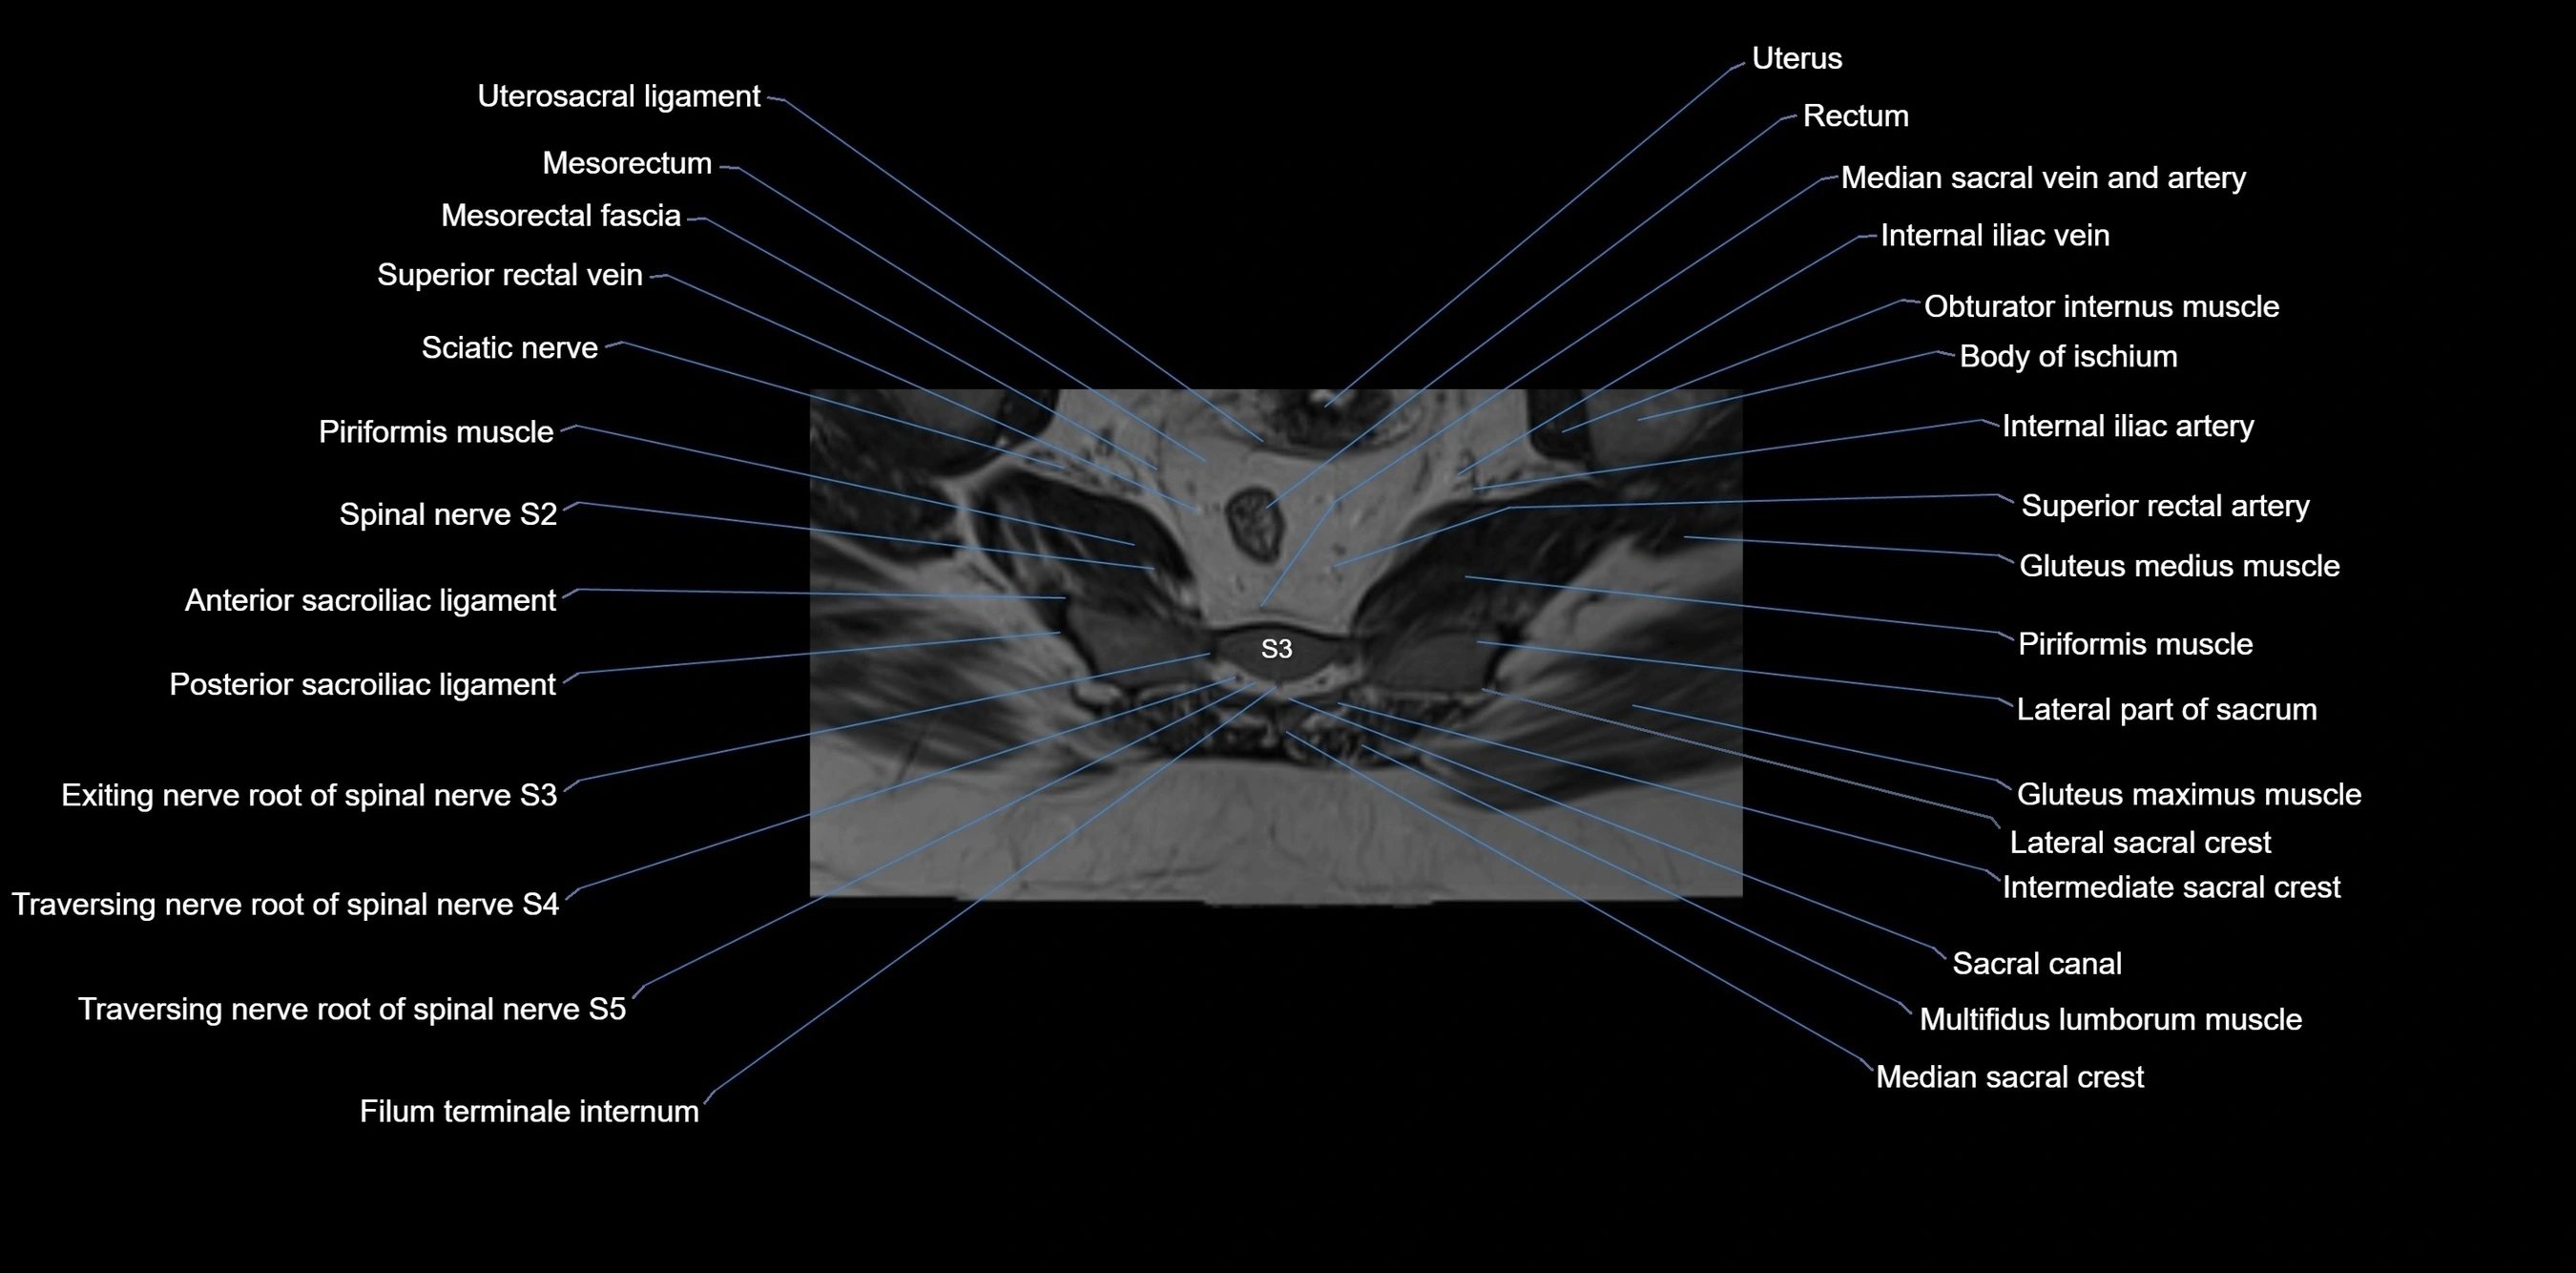

MRI image

image